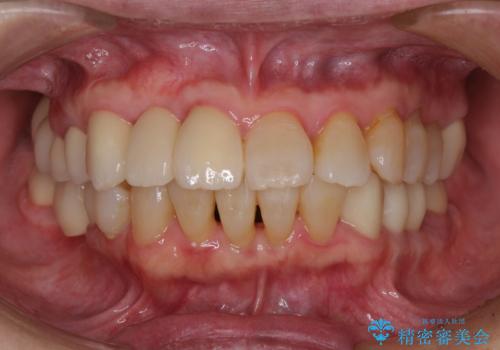

![[MTMを行い歯の神経を保存] 歯周補綴ブリッジの症例 治療後](https://seimitsushinbi.jp/wp/wp-content/uploads/2021/04/75330aaa19199048b71f28658fe46b5b-1-500x350.jpg?v=1618452202)